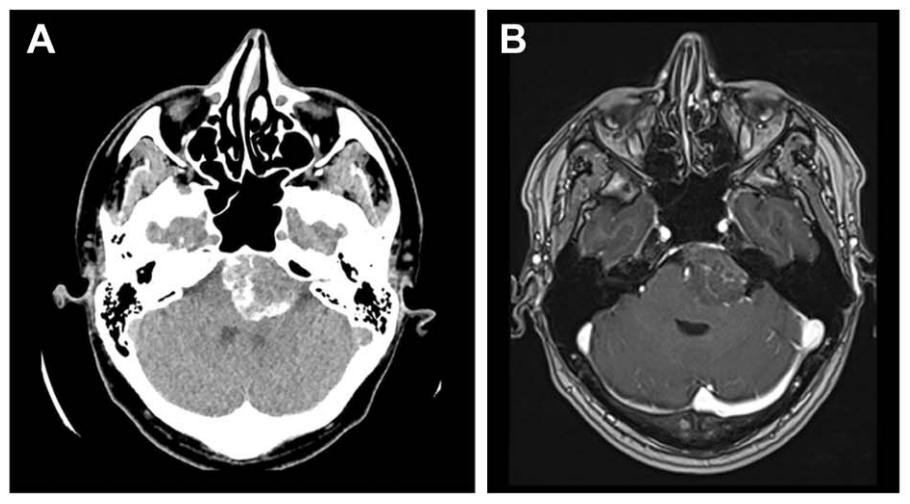

脑膜瘤属于富血供肿瘤类型,血供可同时来源于颅外和颅内循环系统。手术切除可能导致显著出血,出血量范围在200毫升至2.2升之间。栓塞术被提出作为有效的术前辅助治疗手段,旨在降低手术难...